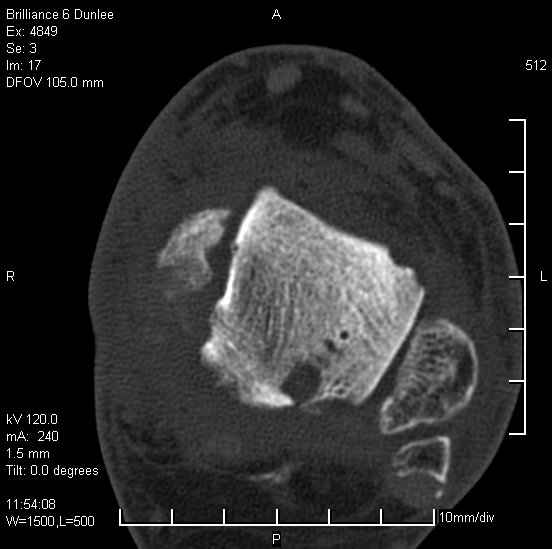

На лечении находится пациент 35 лет. Травма в сентябре 2008 г.- открытый вывих таранной кости

В день травмы ПХО, вправление вывиха, трансартикулярная фиксация. Рана зажила первично. С января нагрузка на конечность. С конца апреля- болевой синдром. На рентгенограммах и КТ признаки ас. некроза таранной кости, артроз подтаранного и голеностопного суставов.

У больного тотальный ас. некрох блока таранной кости, заинтересованы голеностопный и подтараный суставы. Эндопротезирование маловероятно на некротизированную кость. Изолированный подтаранный артродез таран не спасет.При артродезе всю некротизированную кость придется убрать.А далее замещение либо за счет большеберцовой кости, или удлинение на регенерате.